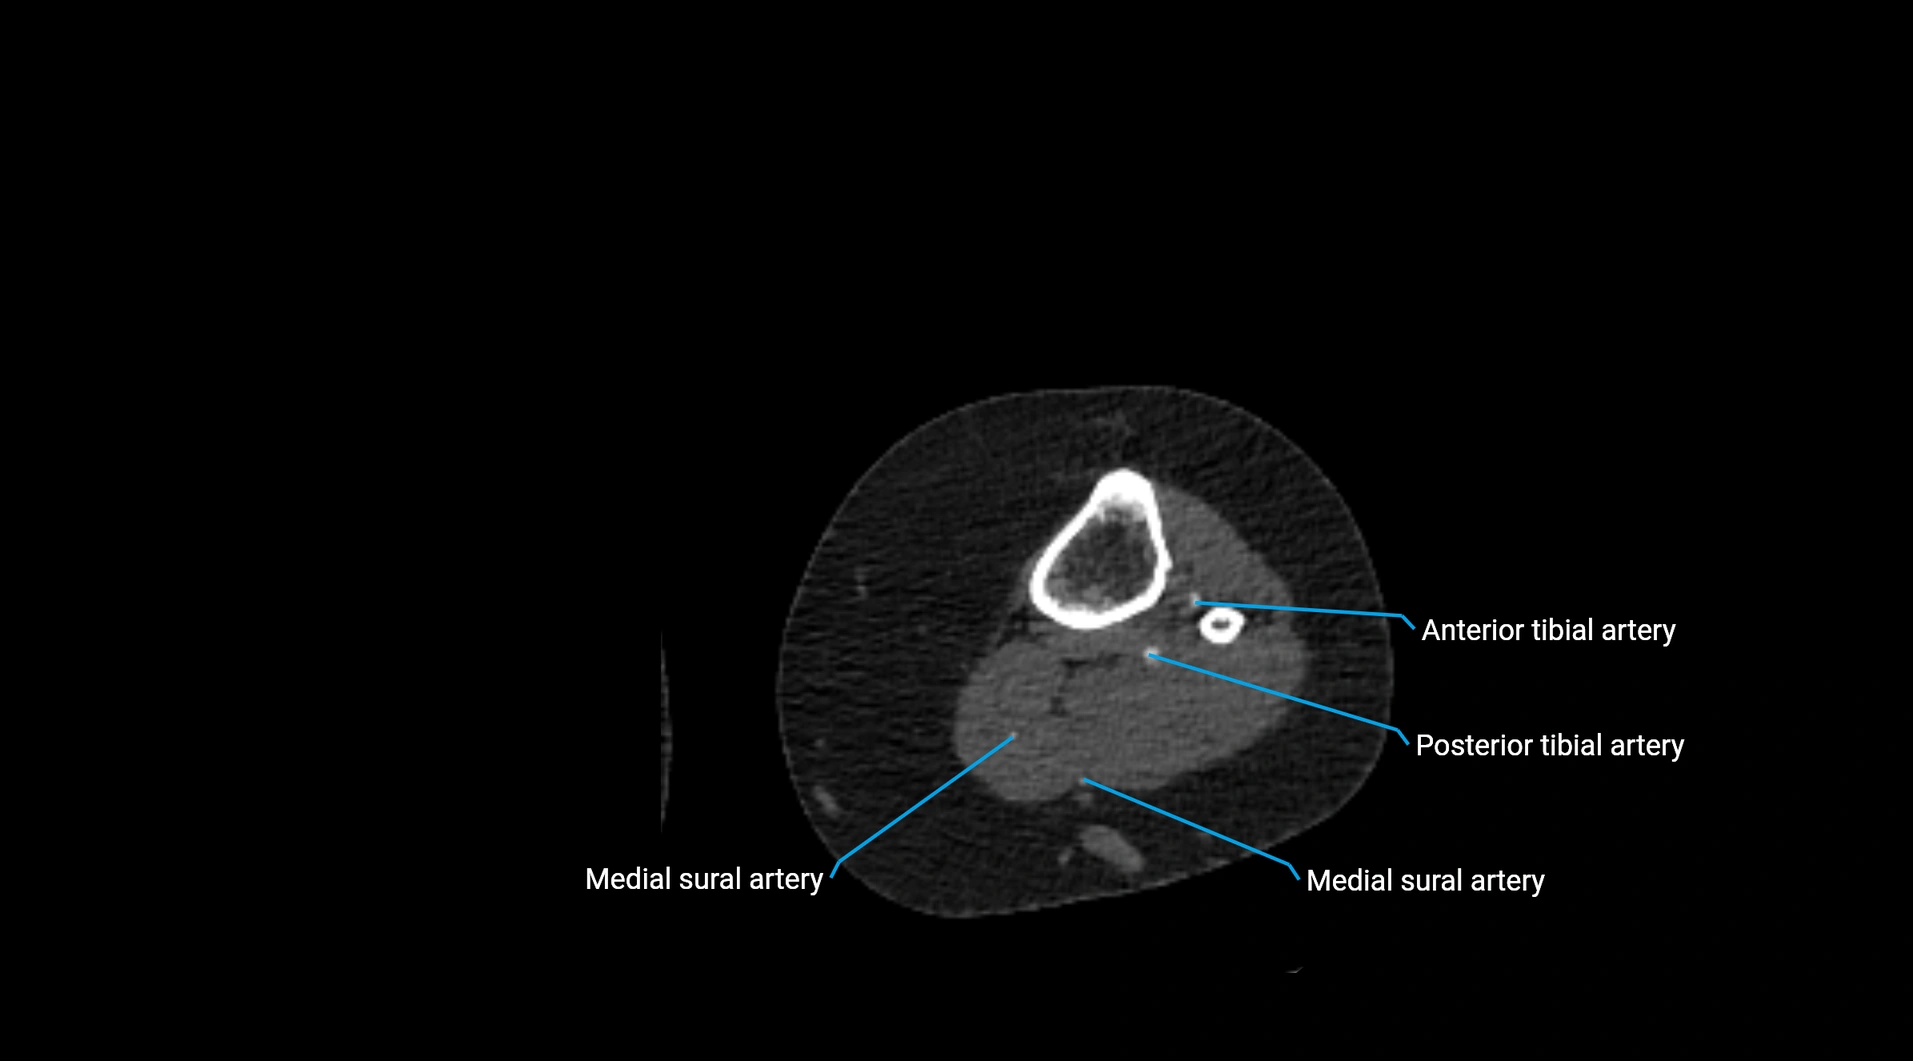

MRI images

image